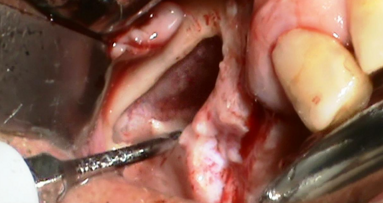

La chirurgia orale, e in particolare la chirurgia dell’ottavo inferiore, costituisce alcuni dei momenti più complessi dell’attività odontoiatrica e, nonostante i più sofisticati e attenti accorgimenti clinici e profilattici, non è priva di rischi e complicanze. L’odontoiatra ha l’obbligo, per quanto possibile, di prevenire, gestire e/o saper fronteggiare eventuali complicanze ed errori.

Negli ultimi anni le tecniche chirurgiche si sono evolute, ma risultano stabili le percentuali degli esiti negativi indesiderati, esiti che rappresentano una delle più comuni cause di contenzioso tra odontoiatra e paziente. È possibile rilevare intenti speculativi da parte di alcuni pazienti e anche condotte censurabili da parte di alcuni colleghi, ma il problema è di fatto più complesso e di non facile risoluzione, soprattutto in un Paese come l’Italia, dove il livello medio di professionalità e competenza risulta piuttosto elevato. L’argomento di fatto è spinoso e, purtroppo, non di rado, al di là delle problematiche di oggettivazione e di quantificazione/qualificazione del danno, l’operato professionale risulta non difendibile a fronte all’impossibilità di documentare e provare diagnosi appropriate, indicazioni cliniche, adeguata gestione dell’intervento e dell’eventuale complicanza/errore, correttezza ed efficacia delle relazioni interpersonali nella relazione di cura, anche attraverso i messaggi e le informazioni trasmesse (consenso).

In buona sostanza, elementi che solo marginalmente possono apparire marginali, di fatto condizionano il rapporto con il paziente e la sua risposta a eventuali esiti diversi da quelli sperati. Molti elementi assumono rilevanza in caso di valutazione medico-legale, valutazione che ovviamente avviene a posteriori, e come tale spesso condizionata più degli esiti che da una serena e appropriata valutazione dell’iter diagnostico-terapeutico. Ne derivano l’opportunità e l’utilità di una corretta pianificazione degli interventi estrattivi a partire dalla fase diagnostica, dalle valutazioni delle effettive indicazioni all’intervento e, in caso di evento negativo, dalla capacità di gestione di esiti.

Oggi si tende a valutare con maggior rigore le effettive indicazioni terapeutiche all’intervento estrattivo in termini di appropriatezza anche della tipologia di intervento eseguito, indipendentemente dalle modalità in cui l’odontoiatra ha operato. In buona sostanza, risulta importante poter stabilire se l’estrazione eseguita sia stata necessaria, utile, opportuna, indifferente, inutile o addirittura dannosa, in poche parole “appropriata”.

Le controversie in materia di indicazioni terapeutiche sono piuttosto accese, ma risulta opportuno e utile per il professionista documentare e motivare secondo logica le diverse scelte comportamentali, escludendo scelte azzardate o inutili, ma anche, talora, dannosi comportamenti prudenziali, sulla base di un’approfondita conoscenza dell’anatomia, della fisiopatologia e anche del singolo paziente, della sua psicologia e delle sue necessità. Non è mai da sottovalutare il caso di incorrere in importanti complicanze anche con atteggiamenti non interventisti, laddove contrariamente si possano rilevare chiare indicazioni all’estrazione, sebbene complessa e ad alto rischio. Piuttosto che dover intervenire d’urgenza o rammaricarsi a posteriori per esiti, parimenti importanti, di una condotta omissiva (sempre censurabile e, qualora provata, giuridicamente perseguibile), valutare le indicazioni e le opportunità d’intervento può risultare clinicamente, deontologicamente, eticamente e legalmente corretto. Non è, al contrario, inopportuno delegare per competenza colleghi più esperti e capaci in caso di riconosciuti limiti o timori.

Un “cattivo risultato”, l’evidenza di una complicanza o di un errore, non costituiscono di per sé evidenza di condotta erronea, negligente e imperita. Né tale esito si pone necessariamente in rapporto di nesso causale con una condotta inidonea del professionista. Esiste la possibilità che si verifichino eventi che, benché possibili e prevedibili, risultino imprevenibili (complicanze, casi fortuiti) anche a fronte di diagnosi adeguate, di condotte chirurgiche ineccepibili, che tuttavia il professionista deve poter provare (rilevanza della documentazione) assieme alla condivisione della scelta terapeutica con il paziente adeguatamente informato (e non superficialmente rassicurato o impropriamente spaventato). La possibilità di complicanze tecnicamente incolpevoli sposta l’interesse sul consenso e su elementi solo apparentemente marginali, indipendenti anche dagli obblighi deontologici o normativi.